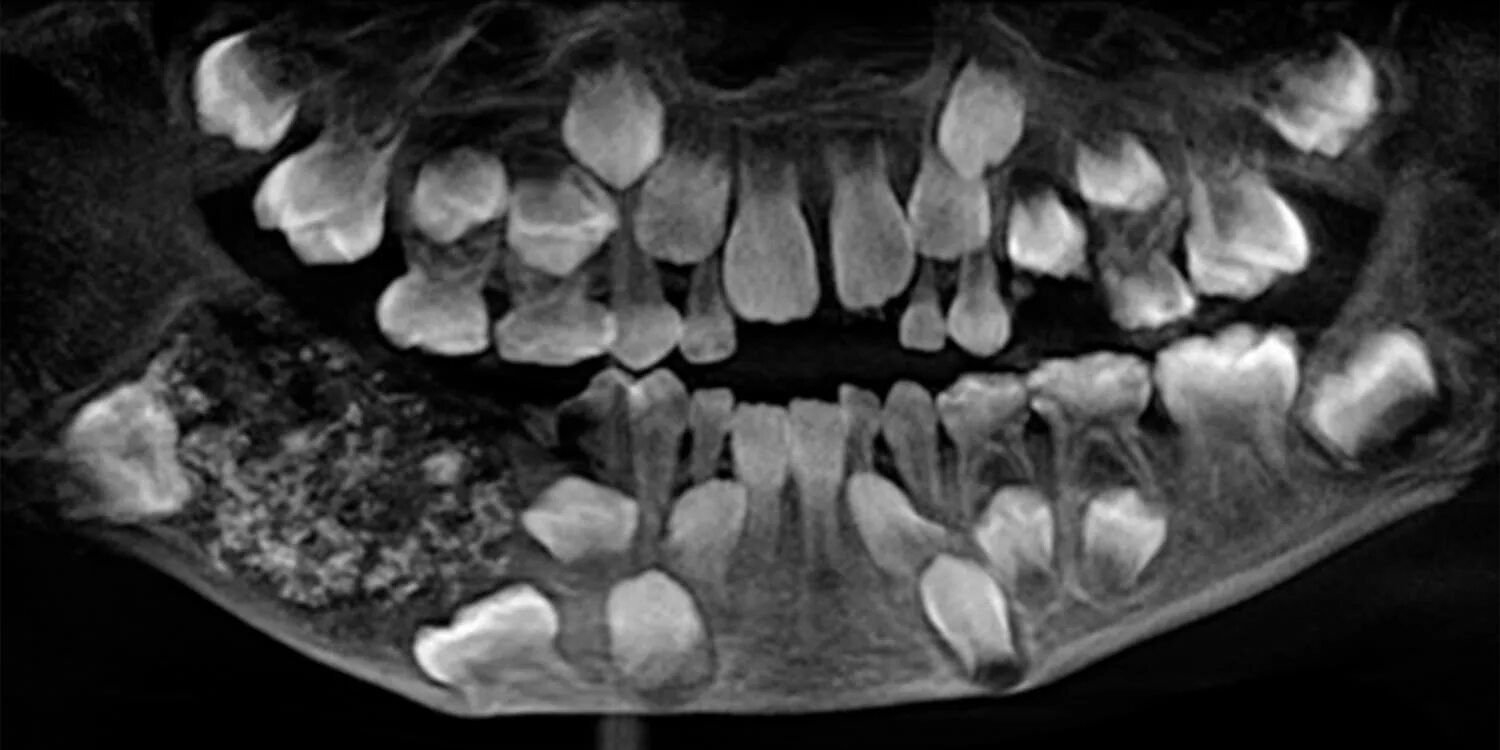

Снимок ротовой полости